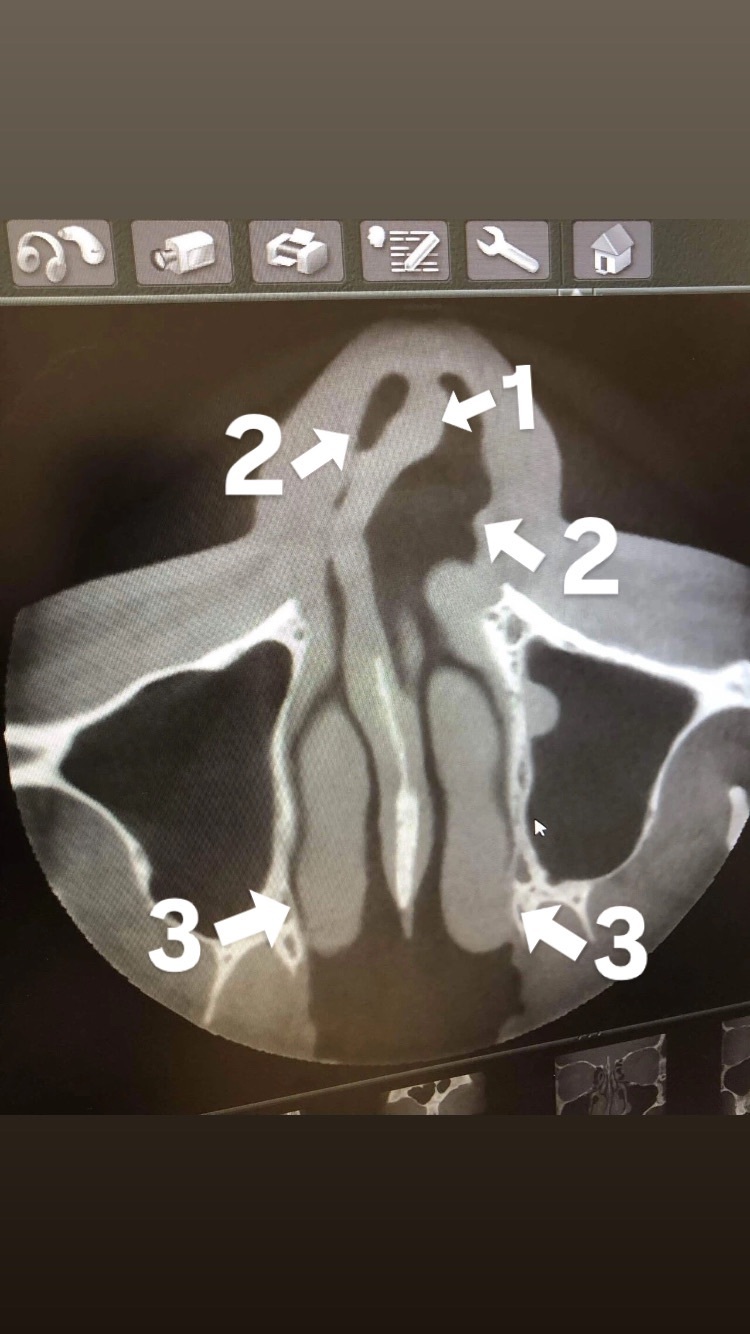

術前の写真

1、鼻中隔軟膏(鼻先の骨、鼻整形もこの部分をいじります)

2、空気の通り道(片鼻は塞がっている状態です)

3、粘膜(アレルギー性鼻炎で腫れてます)

本当に酷かったです。

担当医にも「こんなの見た事ない」ってビックリされました。